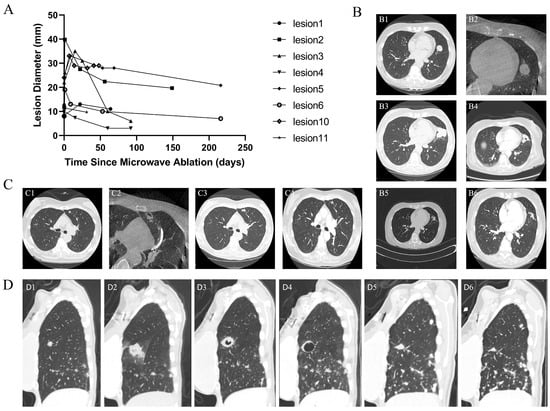

Shape-Sensing Robotic-Assisted Bronchoscopic Microwave Ablation for Primary and Metastatic Pulmonary Nodules: Retrospective Case Series

Background: Bronchoscopic thermal ablation has emerged as a minimally invasive therapeutic option for managing pulmonary nodules in patients unsuitable for surgery or radiotherapy. Robotic-assisted bronchoscopy (RAB) offers enhanced stability and precise navigation, potentially improving the safety and accuracy of bronchoscopic ablation. However, clinical data on RAB-guided microwave ablation (MWA) remains limited. Therefore, further evidence is needed to evaluate its feasibility, safety, and early therapeutic performance. Methods: We conducted a single-center retrospective feasibility study of shape-sensing RAB-guided MWA (ssRAB-MWA) for pulmonary nodules between October 2024 and September 2025. Eligible lesions (≤3.0 cm) included both primary lung cancers and metastatic nodules. All procedures were performed under general anesthesia using the ssRAB system integrated with cone-beam CT for intra-procedural confirmation. Technical success, safety outcomes, and short-term efficacy were assessed. Results: Nine patients (with 11 lesions: 3 primary, 8 metastatic) underwent ssRAB-MWA with 100% technical success. The median ablation time per nodule was 10 min (range, 1–26). One patient developed post-ablation pneumonia requiring hospitalization; no pneumothorax, major bleeding, or airway injury occurred. All lesions exhibited a transient increase in size immediately following MWA, followed by gradual reduction or stabilization over time. PET-CT evaluation demonstrated metabolic remission in primary lesions, with one patient achieving pathologic complete response after surgery. Conclusions: ssRAB-MWA appears to be a feasible and safe navigation-guided technique for small pulmonary lesions, offering encouraging early local control in both primary and metastatic lung cancers. This platform may expand the therapeutic spectrum of interventional pulmonology, bridging diagnosis and local therapy. Larger multicenter studies are warranted to validate long-term outcomes. Full article

Figure 1